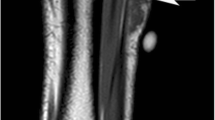

Radiographs are part of the initial evaluation of bone and soft tissue lesions [1]. While advanced imaging modalities, like MRI, continue to improve and are more accessible than ever, radiographs still provide valuable diagnostic information and should not be overlooked. For bone lesions, standard practice involves obtaining radiographs of the entire bone in two orthogonal projections with the adjacent joint. Key imaging features—including bone destruction pattern, zone of transition, cortical destruction, type of periosteal reaction, matrix and tumor mineralization, and soft tissue involvement—help differentiate indolent from aggressive bone tumors and identify a histologic character (Fig. 1) [2]. While radiographs are seldom diagnostic for soft-tissue lesions, they remain a key component of evaluating soft tissue tumors, many of which have distinctive patterns of mineralization. For example, hemangiomas may contain phleboliths, liposarcomas can contain large coarse calcifications, and synovial sarcomas tend to have coarse calcifications that are amorphous or spiculated [3]. Radiographs may also assist in identifying bony erosion from soft tissue sarcomas adjacent to the bone.

A 24-year-old man with a small painless mass on his left anterior tibia just distal to the knee. Lateral (A) and AP (B) radiographs of the left tibia and fibula show an aggressive skeletal lesion (arrow) with osteoid matrix (asterisk) in the left proximal tibial diametaphysis. Close up of the lateral view (C) shows aggressive periosteal reaction (dashed arrow)

A 24-year-old man with a left proximal tibial osteosarcoma (same patient as in Fig. 1). Axial noncontrast CT (A) and volume rendered 3D CT (B) images of the left tibia provide details regarding osteoid tumor matrix and cortical destruction (arrows)